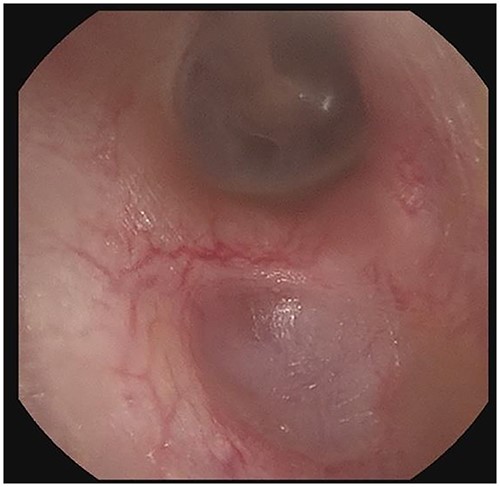

Patient B, a 56-year-old male, was initially diagnosed in 11/2019 and has been consistently followed for 35 months. He was also referred for cerumen impaction in the left ear canal, associated with otorrhea and hearing loss. He was diagnosed with an erosive indentation in the inferior wall of his external auditory canal, filled with ceruminous debris and minimal amount of drainage. Albeit minor, there was obvious bony sequestration in the area of the lesion and miniscule osseous fragments were retrieved from the indentation with a microsuction (Fig. 3a). He was initially followed every 6 months, but his serial debridement was eventually adjusted to every three months, due to his more severe clinical presentation. His symptoms remained mild at all times, including mild intermittent otorrhea on the left side, which was treated as it occurred, with a short course of ototopic quinolone. Interestingly, the patient was noticed to have a similar but smaller lesion (erosive indentation in the inferior wall of his external auditory canal) on the contralateral side, which was managed on the same manner with serial debridements (Fig. 3b). Patient B has also no history of diabetes or osteoporosis. He has an asymptomatic septal perforation, attributed to remote history of vasoconstrictive substances abuse. His blood pressure medications include amlodipine, also used for prolonged intervals. He has satisfactory control of his symptoms with frequent debridements, especially after his follow-up frequency was increased to every three months.

Panel a shows the indentation of the left external auditory canal with bony sequestration. Picture was after debridement. Panel b shows the right external auditory canal. Less extensive than the left, however, fragmentation and sequestration is also seen.